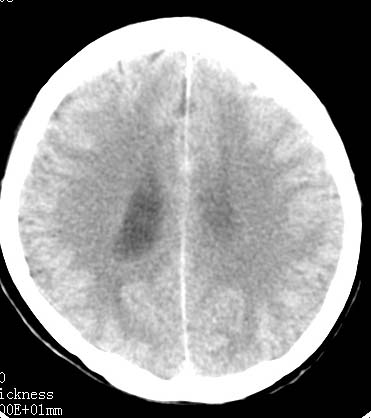

标题: CT9945:男性 病人 请大家看看出血的部位究竟在哪里? [打印本页]

标题: CT9945:男性 病人 请大家看看出血的部位究竟在哪里?

男性 病人 请大家看看出血的部位究竟在哪里?

我觉得是左侧侧脑室体旁出血,破入脑室系统.理由:除了左侧脑室体部外缘不规则之外,还有就是左侧脑室里面出血量较右侧多!

1、原发脑室出血,出血部位应该是左侧侧脑室;

2、左侧基底节区腔隙性脑梗塞;

出血点在左侧脑室旁。